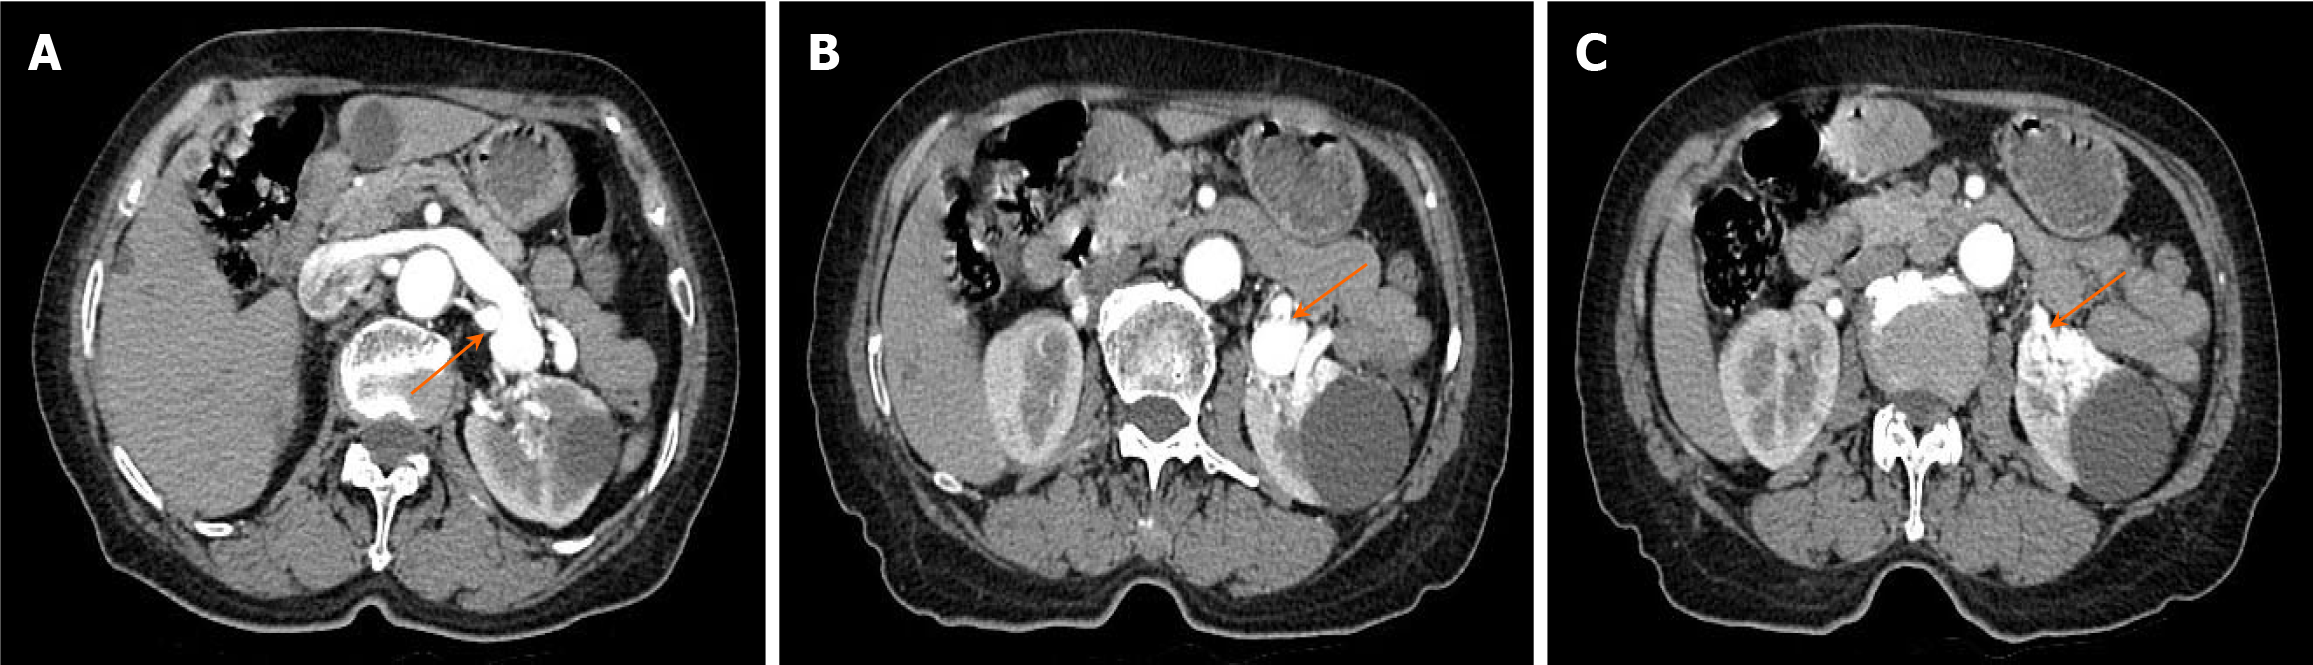

Ultrasound definitely diagnosed the presence of RAVF between the main renal artery and vein. In order to further clarify the presence or absence of RAVF in the tortuous vascular mass of the kidney, more objectively understand the location of the lesion and its anatomic relationship with the surrounding tissues and organs, exclude and identify RAVF caused by other diseases such as renal space-occupying lesions, an enhanced CT examination of the abdomen was performed on June 27, 2023. The scan revealed early visualization of the left renal vein in the arterial phase, with the left renal artery as the blood-supplying artery. The left renal vein was markedly thickened, with localized verrucous dilatation (Figure 4A). The branches of the left renal artery were in communication with the left renal vein, and a rounded low-density shadow was observed in the middle part of the left kidney with a maximum diameter of approximately 4.2 cm, which did not show noticeable enhancement (Figure 4B). A nodular isointense shadow was observed in the middle and lower poles of the left kidney, with a maximum cross-section of 2.9 cm × 2.7 cm. This area showed markedly uneven strengthening, and the left renal artery branch was observed to be in communication with the left renal vein (Figure 4C). Enhanced CT revealed left renal occupancy, with tumor-like dilatation of the adjacent left renal vein, leading to a diagnosis of possible left RAVF.